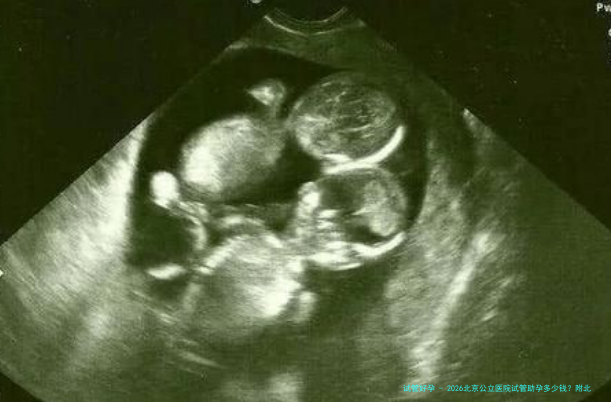

北京医疗学专业从属的医院的试管婴儿技术非常好,目前开展的技术包括用老公的精子进行路之人工授精,第一代和第2代试管婴儿等。许多试管助孕家庭也是对的这家医院的试管婴儿助孕费用感兴趣。这一篇文章将替你解答这个问题。此外我还整合了一份2026年北京试管婴儿的费用明细单,供大家参照。

北京公立医院的试管费用为2026美元。2026年北京公立医院卵子的体外受精费用并不低价,总费用约为六万至八万元人民币。一般来说试管婴儿助孕的具体费用与当地发展水平和医院收费有关。北京公立医院试管婴儿助孕的费用主要包括卵子免费费、试管婴儿检查费、试验室操作费、移植手术费等。60-80,000通常是单次性成功的费用,如果1次移植没有成功,第二次移植的费用自然会增加,以下所示。